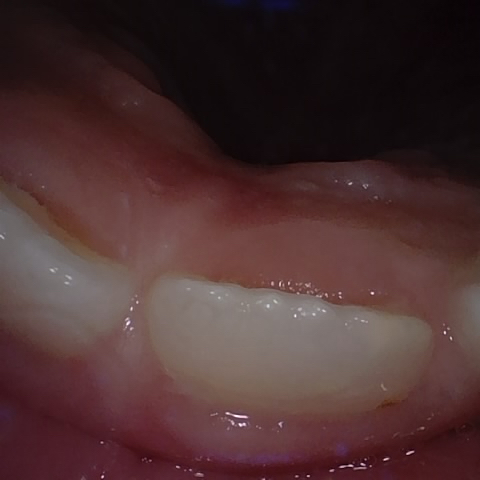

Annotated as "Good"